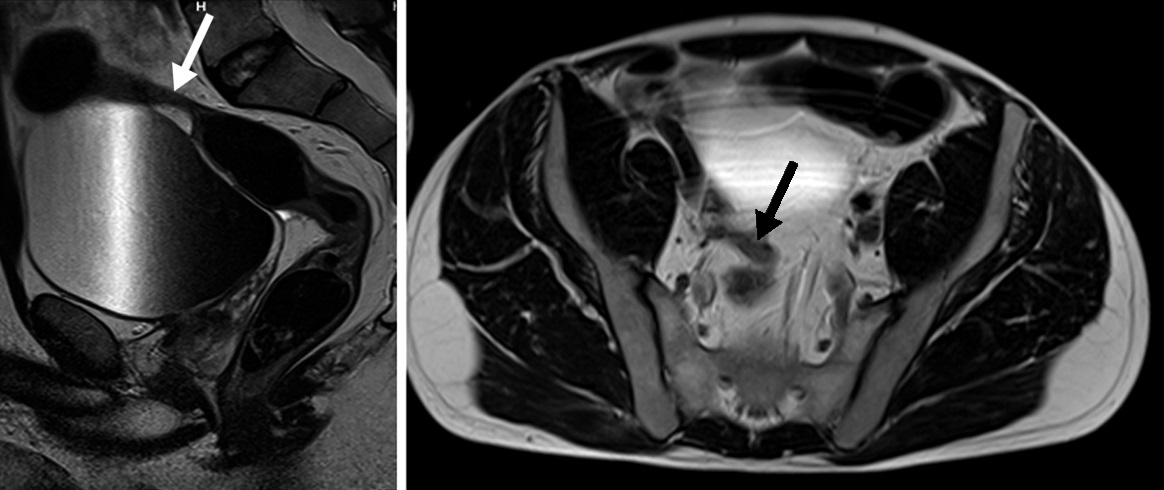

Figura 2

Paciente de sexo masculino de 9 años con antecedente de resección colónica y ostomía por enfermedad de Crohn. a) Secuencia eco de gradiente coronal donde se idenjpgica el engrosamiento parietal del asa detransitada de 6 mm de espesor (punta de flecha).

b) Misma secuencia muestra adenomegalias ileocólicas de hasta 10 mm como elemento de actividad (punta de flecha).

c) Secuencia T2 axial con saturación grasa evidencia edema submucoso como una banda hiperintensa central entre la mucosa y serosa (flecha).